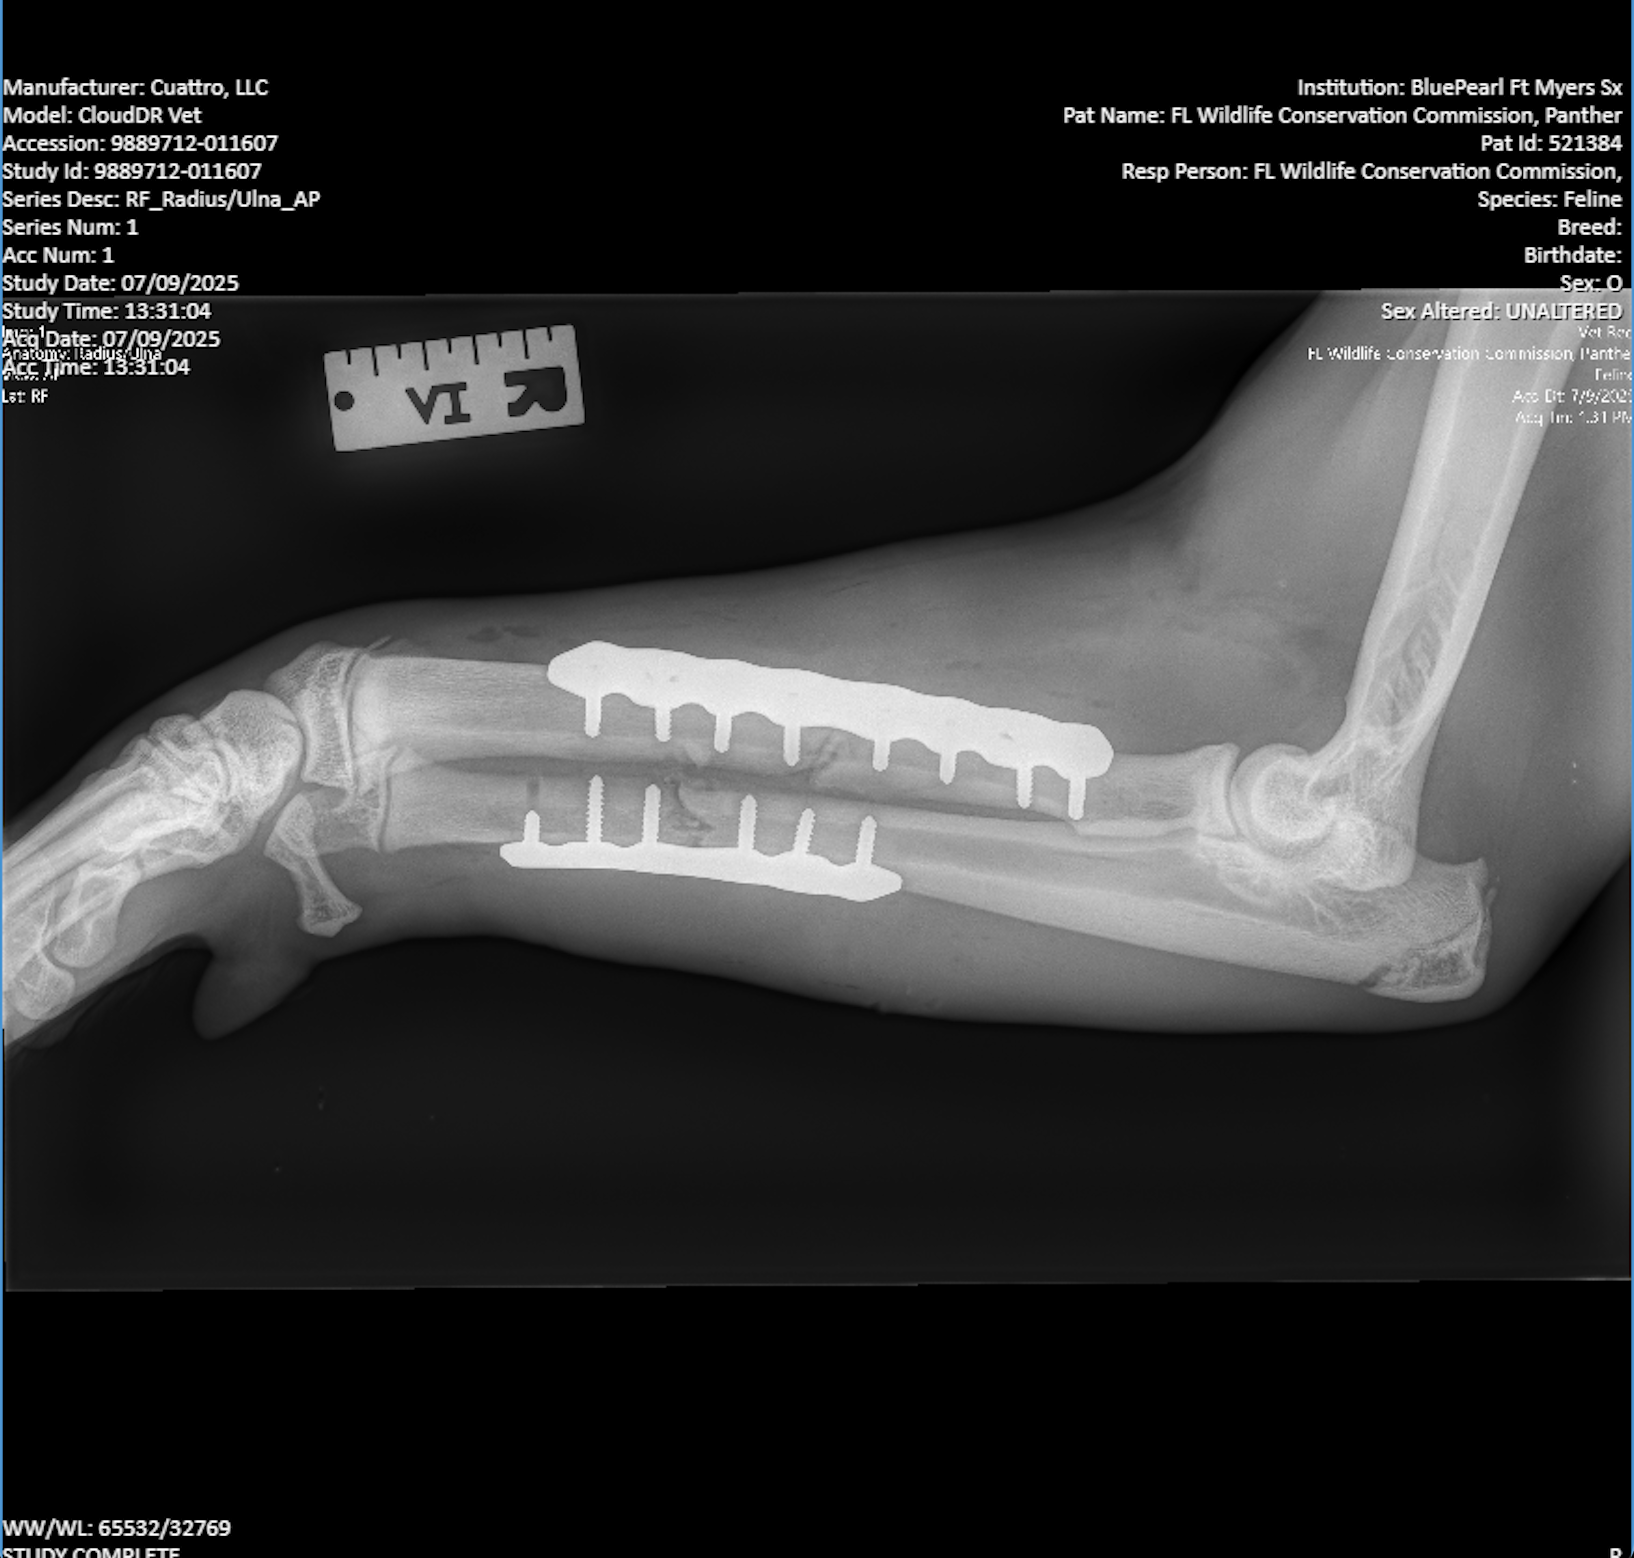

In a press release, Dr. Oscar Carballow said Loper sustained a right radius and ulna fracture. He had some minor lacerations and the doctors stabilized both bones with plates and screws to help repair his leg.